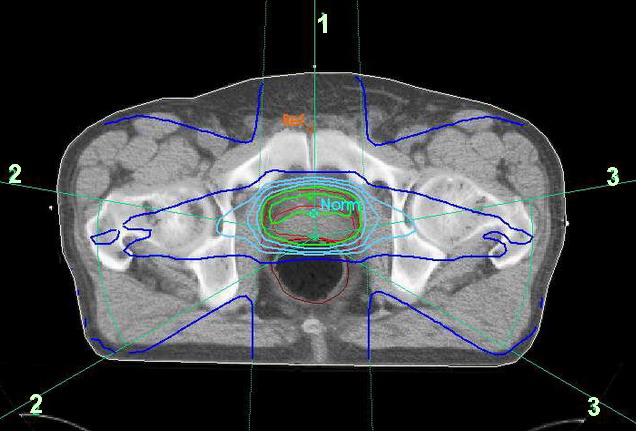

Das Bild zeigt den Isodosenplan einer Bestrahlung mit seitlichen Pendelfeldern und einem ventralen Stehfeld.

Isodosen RT Prostata